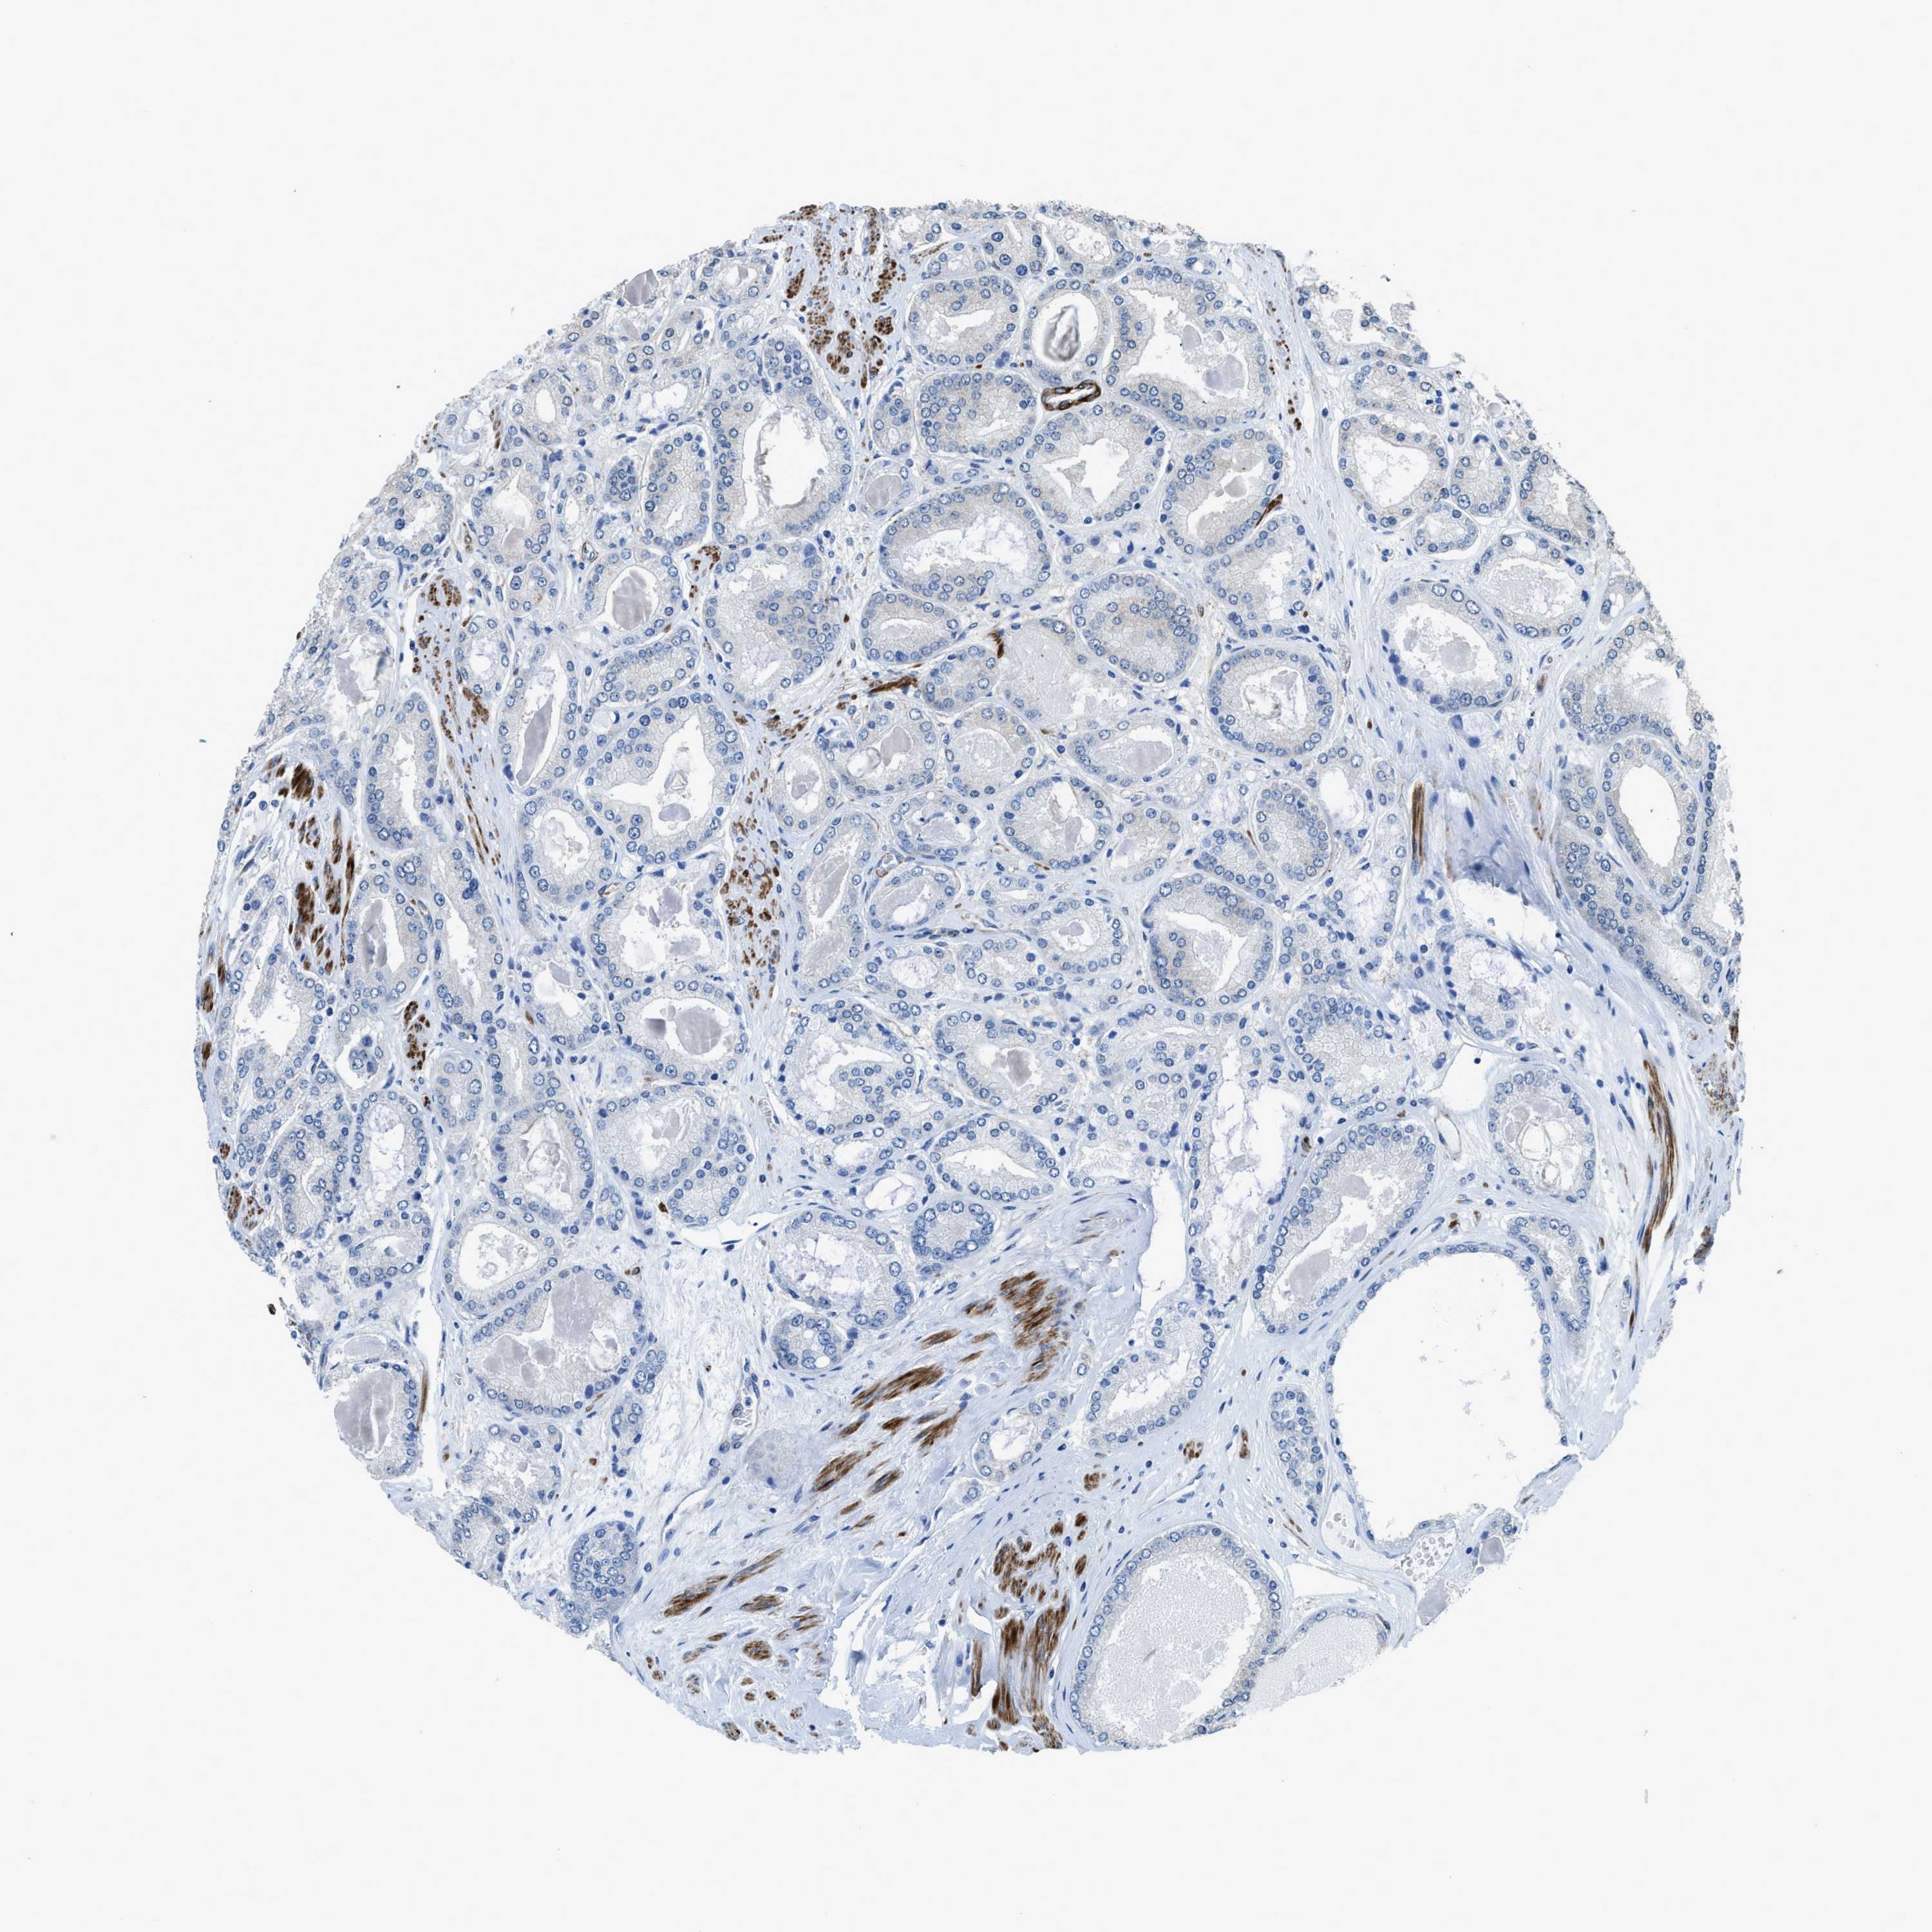

PROSTATE CANCER - Protein expressioni

A mouse-over function shows sample information and annotation data. Click on an image to view it in a full screen mode. Samples can be filtered based on level of antibody staining by selecting one or several of the following categories: high, medium, low and not detected. The assay and annotation is described here.

Note that samples used for immunohistochemistry by the Human Protein Atlas do not correspond to samples in the TCGA dataset.

Antibody stainingi

Antibody staining in the annotated cell types in the current human tissue is reported as not detected, low, medium, or high, based on conventional immunohistochemistry profiling in selected tissues. This score is based on the combination of the staining intensity and fraction of stained cells.

Each image is clickable and will lead to virtual microscopy that enables deeper exploration of all samples and also displays staining intensity scores, fraction scores and subcellular localization as well as patient and tissue information for each sample.

Antibody HPA040066

Antibody HPA044200

Antibody CAB017192

Staining

High

Medium

Low

Not detected

Intensity

Strong

Moderate

Weak

Negative

Quantity

>75%

75%-25%

<25%

None

Location

Nuclear

Cytoplasmic/membranous

Cytoplasmic/membranous,nuclear

Adenocarcinoma, High grade

Adenocarcinoma, Medium grade

Adenocarcinoma, Low grade